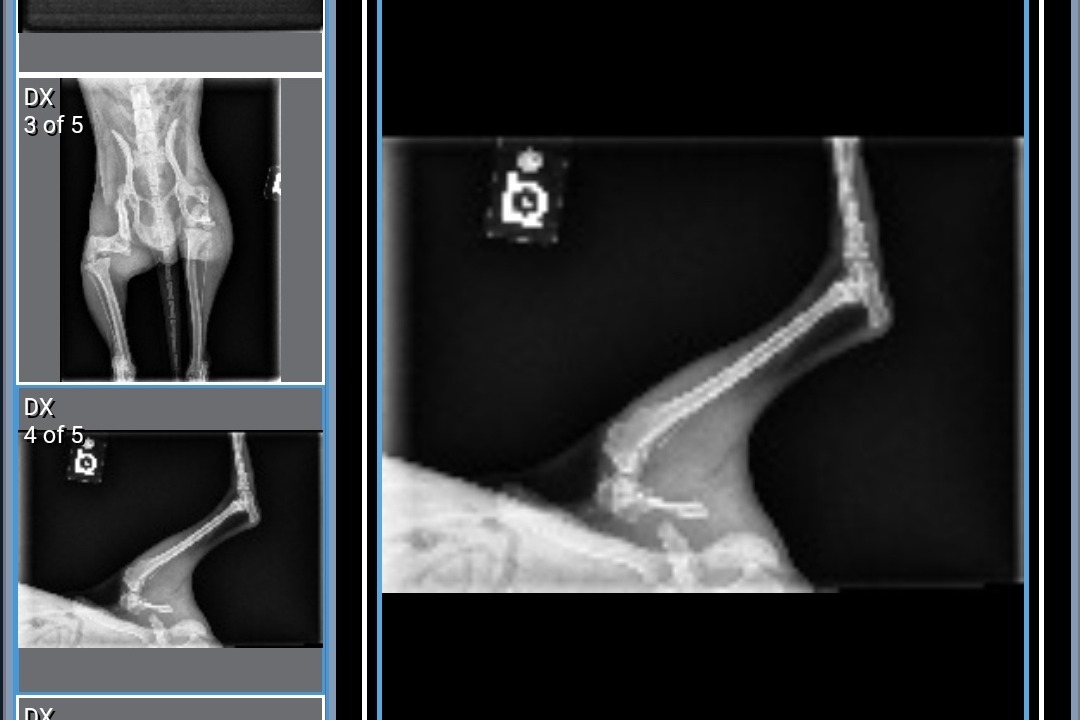

After x-rays, we found out that Mikko had two broken legs. One was an older fracture that had healed improperly and the other was more recent, his leg was completely detached and scraping against his muscle. Due to the fractures, Mikko suffered extensive muscle atrophy and has had to rely on his front legs for mobility. The doctors advised us to proceed with the surgery as soon as possible, stating, "There's still a chance to save his legs but if we wait, we will have to amputate."

The following images are Mikko's x-rays and the first documented photo of him when he was found.